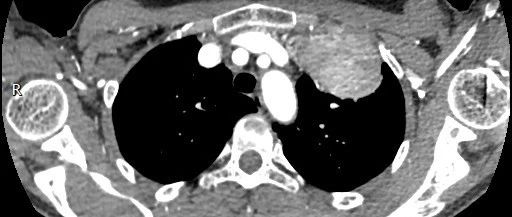

医学影像  yxyx-app  医学影像APP,打造伴随医生快速成长的影像学习社区。与影像园(Xctmr.com)一起提供最全面的影像案例库、基础(解剖、病理、影像诊断)知识、影像技术及考题等,为医生提供最佳的医学影像参考。【所属科室】呼吸科【基本资料】患者,女,20岁【主诉】干咳伴胸痛半月【影像图片】【讨论问题】如何诊断?【医学影像APP用户讨论】评论:左前纵隔见一囊样包块影,内见结节状、条片状脂性密度影,局部囊壁见壁结节影,增强见囊壁及壁结节明显均匀强化;上纵隔脂肪间隙密度增高,但与包块分界尚清,增强后内未见明显强化;肺动脉主干及左侧肺动脉见受压推移,未见充盈缺损影。前纵隔占位,考虑畸胎瘤。...